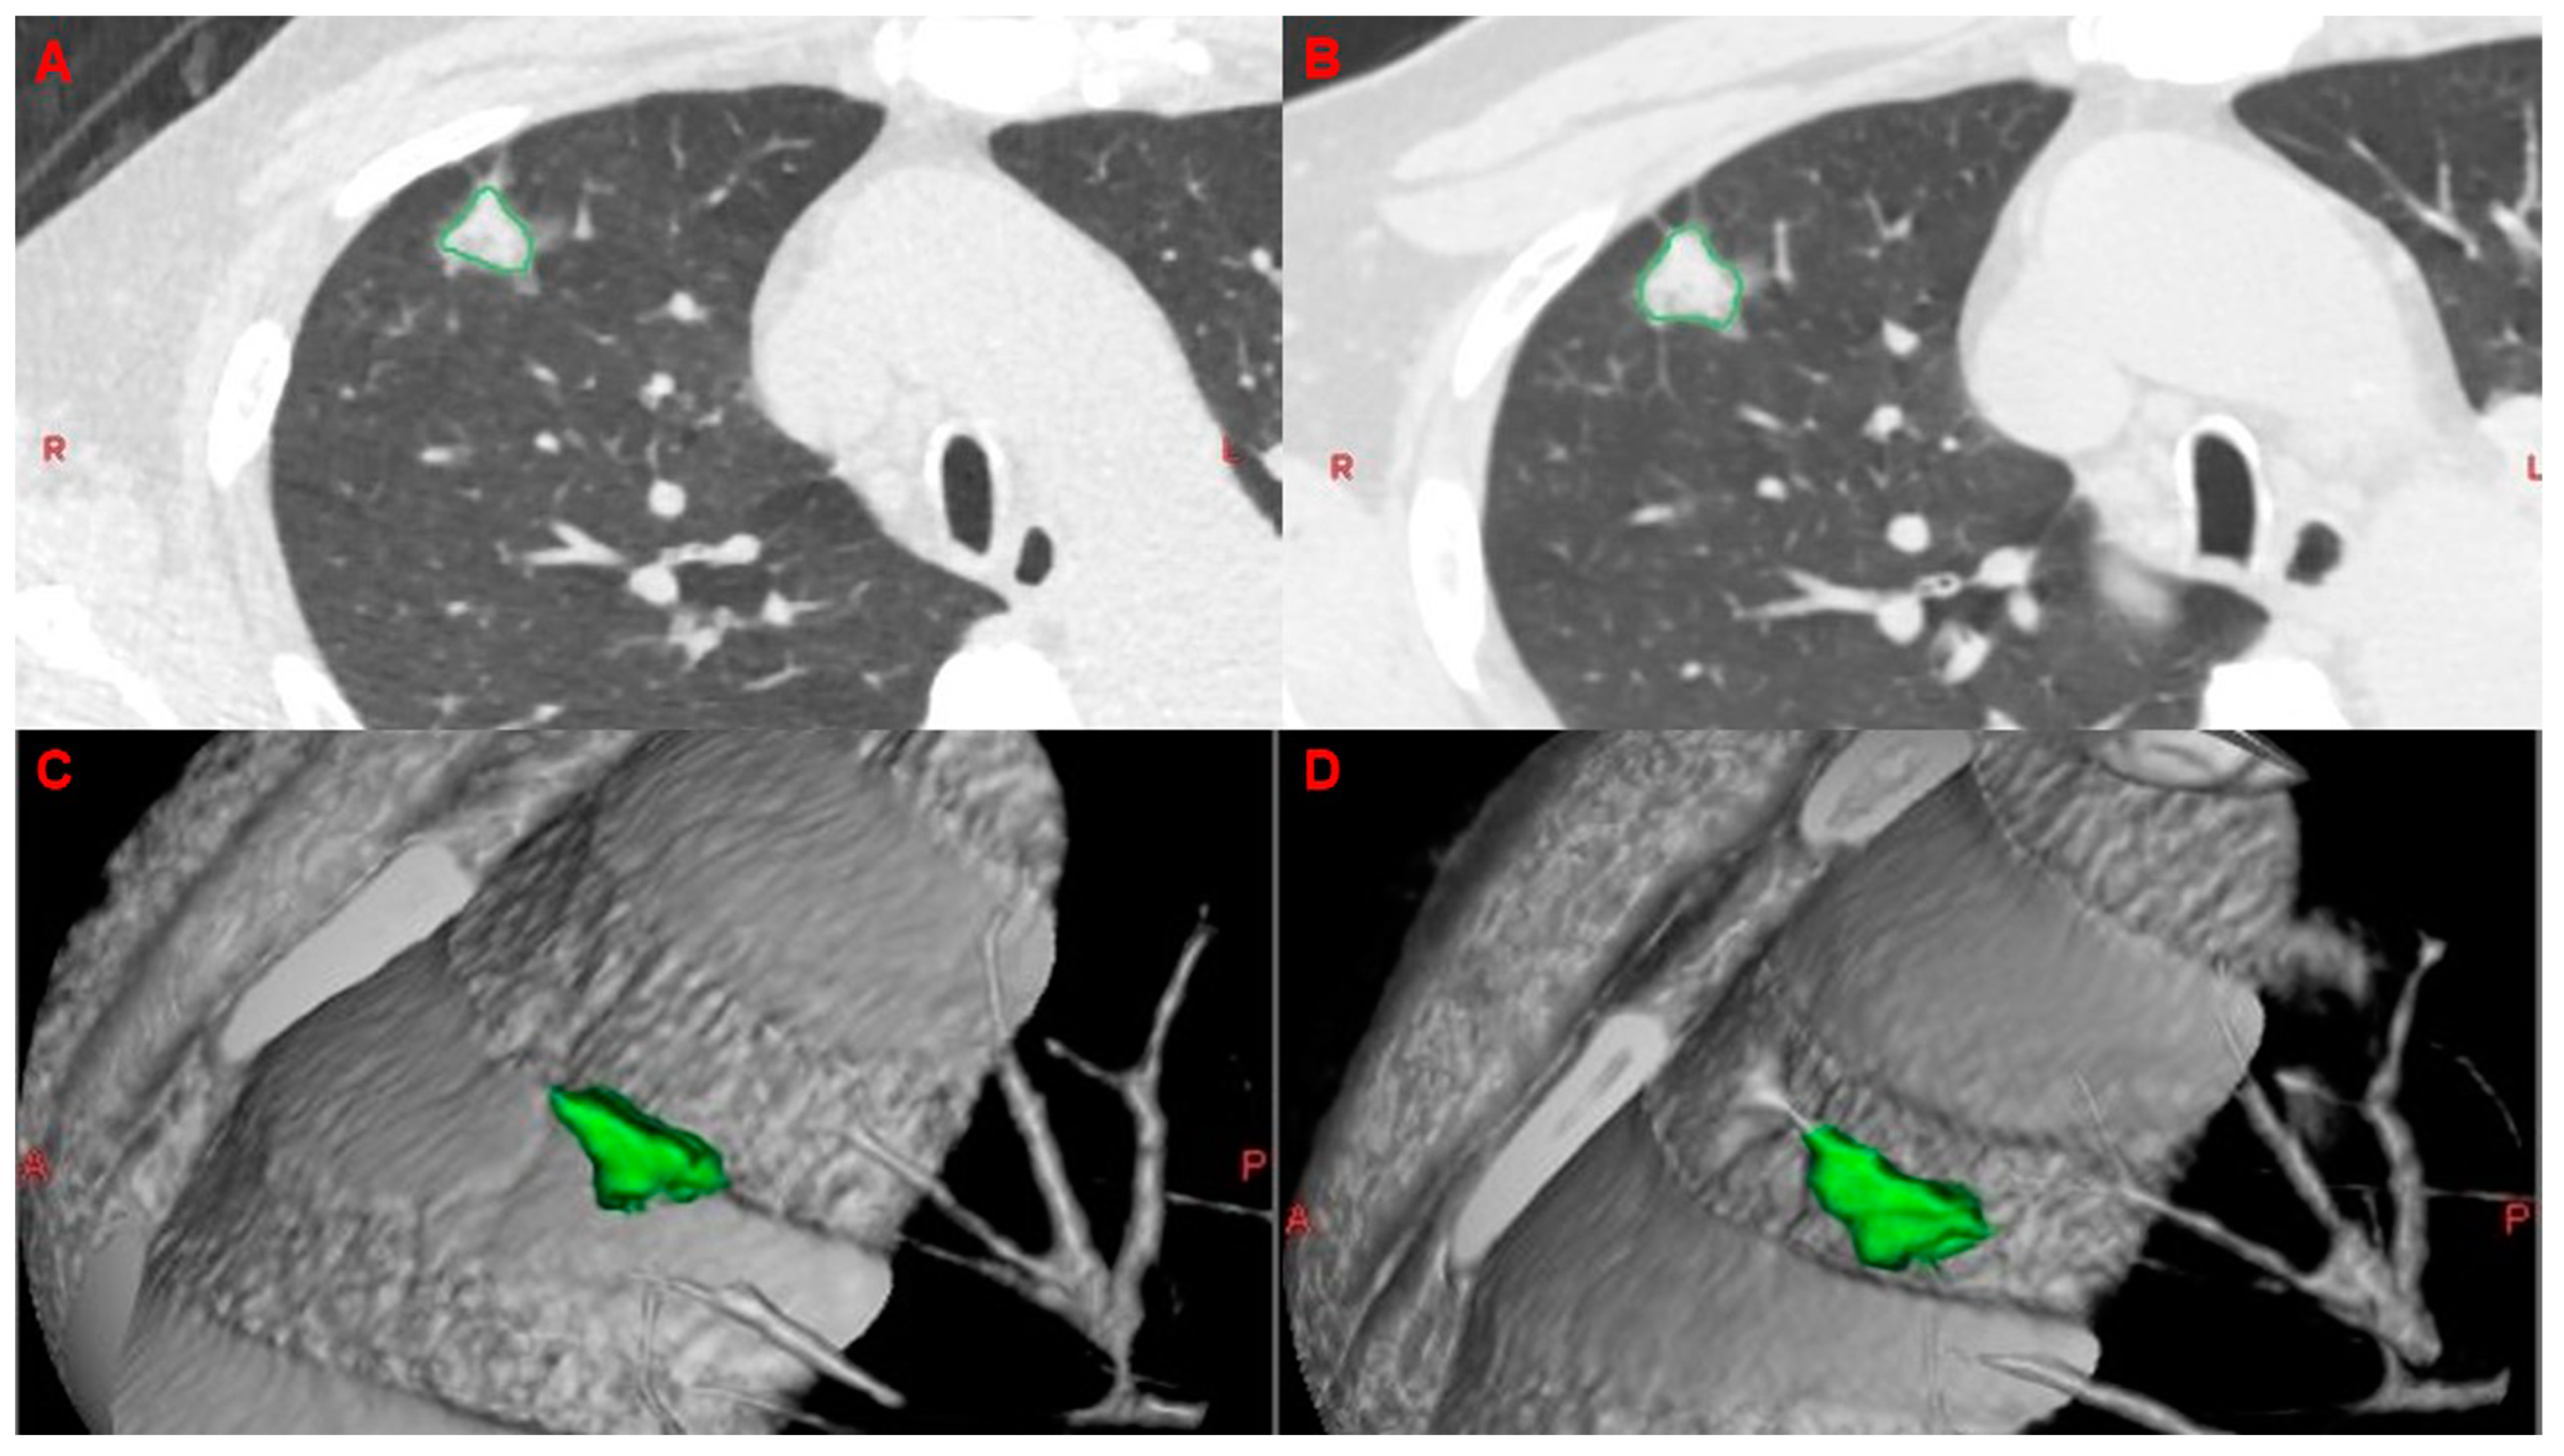

2.5. Analysis of VDTs